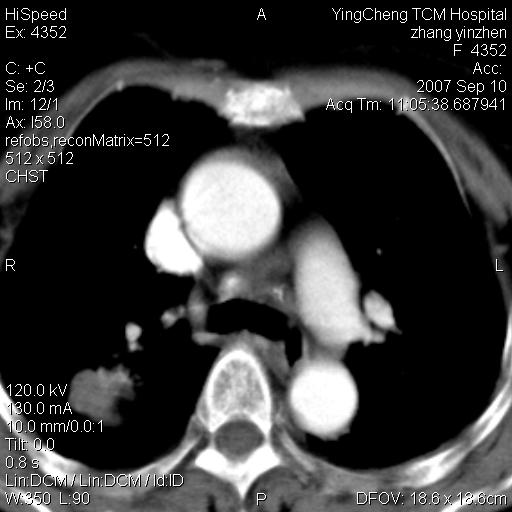

以下是引用卜一在2007-9-18 14:41:00的发言:[br]右肺肿块:毛刺+胸膜凹陷征+供血血管+浅分叶+强化。支持:周围性肺癌 !另:左侧甲状腺腺瘤!

以下是引用夏季在2007-9-18 11:00:00的发言:[br]1。右肺肿块,周围有短毛刺,肺门侧有血管与其相连,胸壁侧有胸膜凹陷征,考虑周围性肺癌 2。左侧甲状腺软组织肿块,内有高密度钙化灶,考虑左侧甲状腺腺瘤。